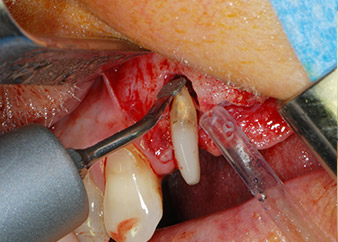

Un mese più tardi, nel giorno programmato per l'intervento, il dolore e l'infiammazione in corrispondenza del dente 24 erano minimi, ma era ancora presente mobilità di classe 2 secondo Miller. Dopo l'apertura dei lembi e la pulizia del tessuto periapicale e periradicolare infetto, l'estensione della mancanza ossea si è resa evidente (Figg. 2 e 3).

Tutto il tessuto osseo vestibolare e distale era mancante in corrispondenza della radice buccale. La possibilità di attacco era essenzialmente ristretta alla radice palatale, evidenziando la prognosi negativa preliminare. Anche il dente 27 mostrava un punto di attacco orizzontale ridotto e una rarefazione apicale minima (cfr. Fig. 1), senza sintomi clinici.

perdita totale di tessuto osseo e attacco

Fig. 2 e 3: Dopo aver sollevato i lembi, un mese dopo il pretrattamento endodontico e l'inizio della terapia periodontale sull'intera dentatura, la radice buccale del dente 24 mostrava una perdita totale di tessuto osseo e di punti di attacco.

Si è mantenuta , tuttavia, l'idea iniziale di conservare entrambi i denti come appoggi temporanei del ponte durante il periodo di sei mesi per l'osteointegrazione degli impianti. In seguito la situazione si sarebbe assestata. In primo luogo, in un tentativo di risolvere il problema entro-periodontale, la superficie radicolare rimanente è stata attentamente sbrigliata con apparecchiatura piezoelettrica (Piezomed di W&H con l'attacco S1 a spatola, progettato in origine per l'erosione della parete laterale del seno mascellare) Fig. 4).

Quindi con lo stesso strumento si è passati ad abradere l'apice per rimuovere il tessuto apicale infetto residuo e per ridurre le possibili ramificazioni radicolari e canalari accessorie (apicetomia) (Fig. 5). Non è stato necessario riempimento retrogrado poiché si era appena ritrattato il riempimento ortogrado.